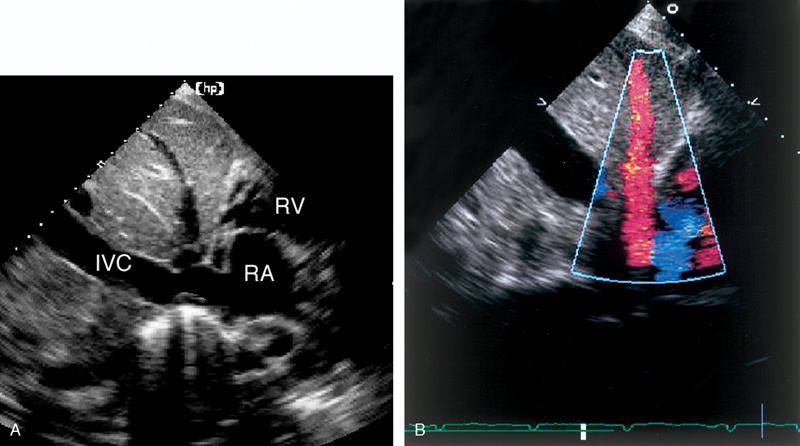

فحوصات تشخيصية لبعض امراض القلب والشرايين التاجية